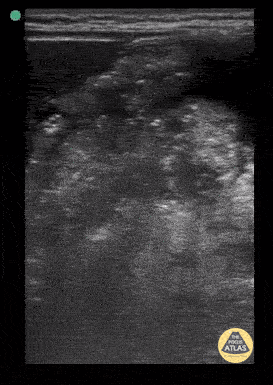

Gastric content eval for patient undergoing procedural sedation. With the patient in the right lateral decubitus position the linear probe is placed in a subxiphoid sagittal axis with the probe marker towards the head. The stomach is seen immediately caudal to the liver. The class 5 layer bowel wall of the stomach can be seen containing large volume, mixed echogenicity content. Contributor: Matthew Moake, MD PhD